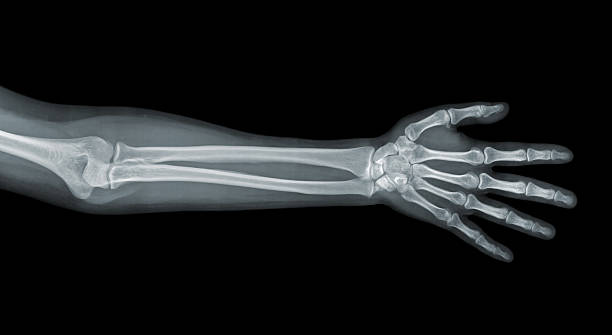

Una radiografía es una prueba que toma imágenes de las estructuras internas del cuerpo. Para poder obtenerlas utilizamos rayos X que pasan a través del cuerpo y crean imágenes de los huesos y sus órganos con fines de diagnóstico. Es una prueba indolora y rápida.

Tipos de RADIOGRAFÍAS:

• Extremidades superiores: Brazo, Antebrazo, Mano, Muñeca, Dedos